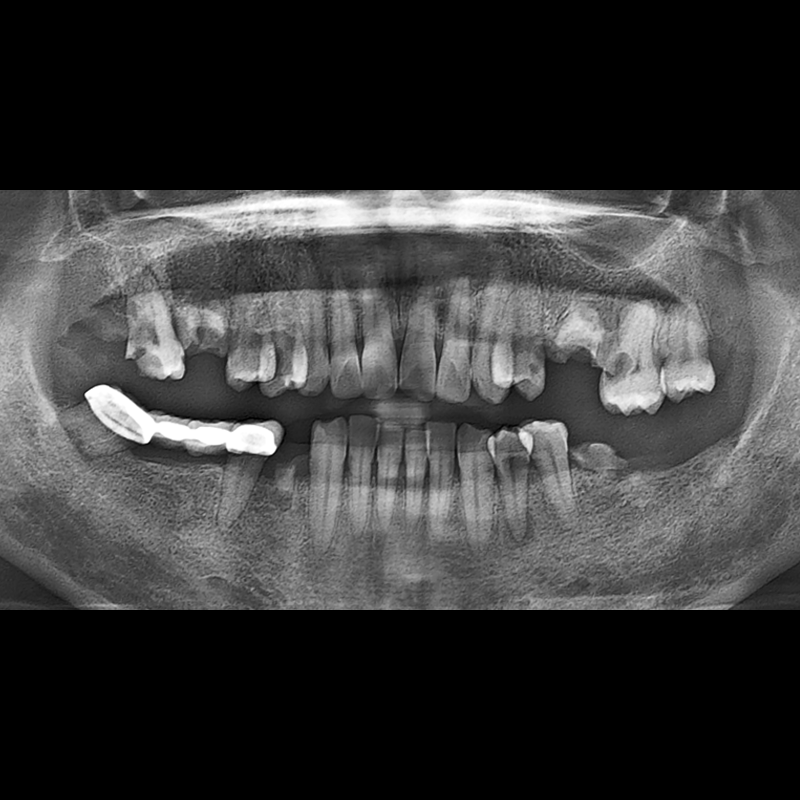

IMPLANT

BEFORE AFTER